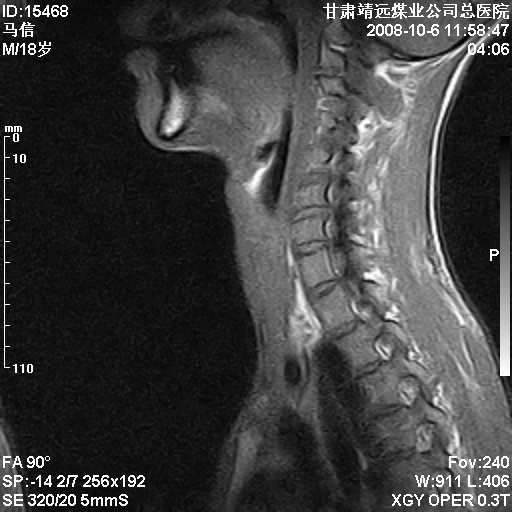

标题: MRI1827:颈椎内异常信号,是不是占位。

患者18岁,学生,在玩耍中受伤来检查,患者喜欢打篮球。颈椎内异常信号影,我们考虑占位,但是不像占位,又考虑硬膜囊的增厚,大家关建看颈椎椎管内的那个异常占位信号

考虑 c3-4 c4-5 c5-6椎间盘突出,l3-4 l4-5 l5-s1椎间盘变性

后纵韧带增厚,颈2/3、3/4、4/5、5/6椎间盘变性、突出;椎体有旋转,提示椎小关节有问题;腰椎间盘变性,许莫氏结节。